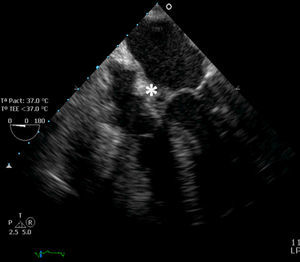

Bloqueo auriculoventricular de primer grado, de segundo grado Mobitz I y, posteriormente, con conducción 2:1. Ecocardiograma transesofágico: válvula aórtica bicúspide que prolapsa y ocasiona insuficiencia aórtica grave; seudoaneurisma en el seno coronariano derecho (*), que afecta a la unión mitroaórtica. Endocarditis aórtica subaguda con trastorno secundario de la conducción auriculoventricular (figura).